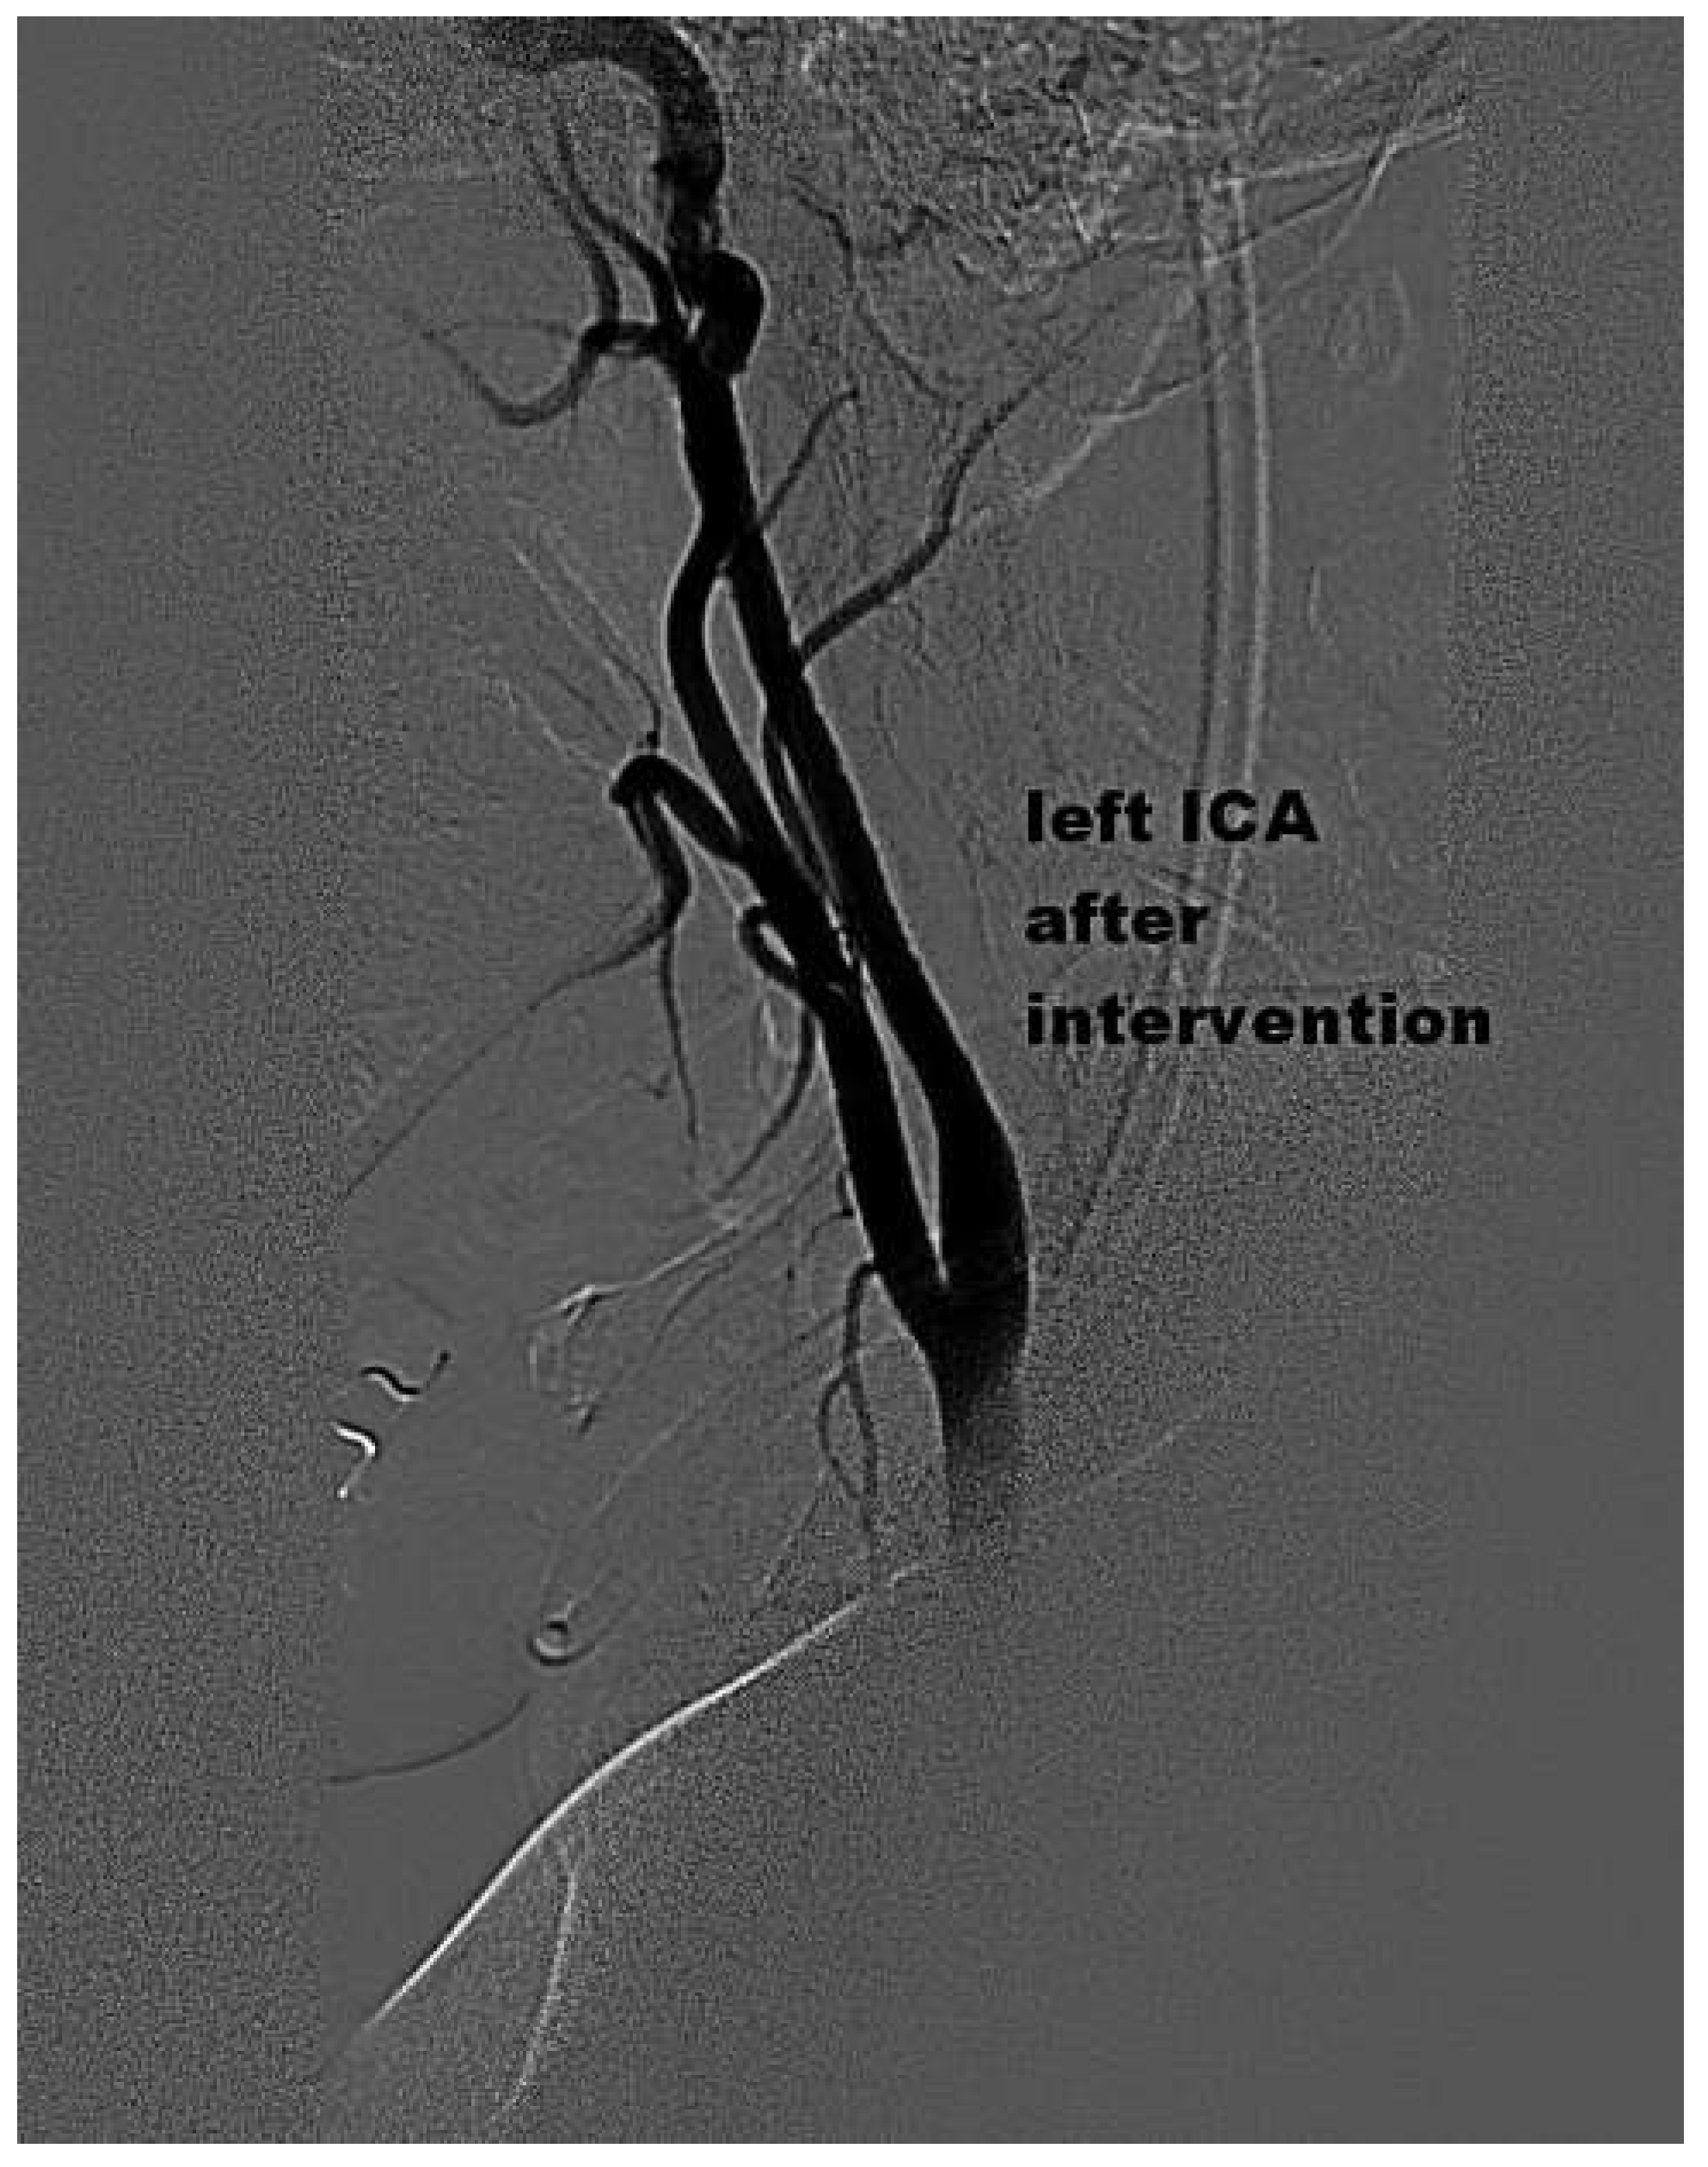

Mechanical Thrombectomy After Embolic Internal Carotid Artery Occlusion in Acute Stroke

Case presentation